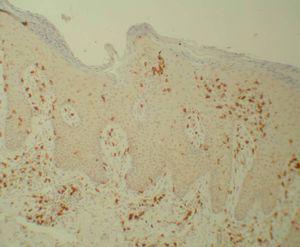

Se analizó un total de 20 biopsias procedentes de 10 pacientes. La cuantificación de las poblaciones linfocitarias totales, en el estrato dérmico y en el estrato epidérmico, se muestran en la tabla 1. Hubo un descenso significativo en las distintas poblaciones linfocitarias tras el tratamiento con etanercept. Los linfocitos CD4 totales basales y tras tratamiento con etanercept mostraron 16,93 ± 8,13 frente a 6,51 ± 3,46, p < 0,007; y los linfocitos CD8 totales basales y tras tratamiento (figs. 1 y 2) con etanercept: 17,73 ± 9,77 frente a 10,50 ± 9,46, p < 0,005. Los linfocitos CD4 basales en dermis y tras tratamiento con etanercept registraron 14,46 ± 6,42 frente a 6,11 ± 3,41, p < 0,007; y los linfocitos CD8 basales en dermis y tras tratamiento con etanercept: 17,29 ± 7,17 frente a 11,57 ± 6,50, p < 0,005. Los linfocitos CD4 basales en epidermis y tras tratamiento con etanercept registraron 2,47 ± 2,18 frente a 0,40 ± 0,29, p < 0,008; y los linfocitos CD8 basales en epidermis y tras tratamiento con etanercept: 17,73 ± 9,77 frente a 10,50 ± 9,46, p < 0,005.

Figura 1. Linfocitos CD8 antes del tratamiento (Bond Polymer Detection System 200x).

En nuestro estudio encontramos un descenso precoz del número global de linfocitos T en las lesiones de psoriasis tras 12 semanas de tratamiento en monoterapia con etanercept, lo que concuerda con los resultados de Gottlieb et al16 tras 24 semanas de tratamiento. Este descenso se produjo tanto en los linfocitos CD4+ como en los linfocitos CD8+ en dermis y epidermis, pero no en sus respectivas poblaciones sanguíneas. El descenso de linfocitos T en las lesiones tras el uso de anti-TNF también se ha constatado en modelos animales y sugiere que la proliferación local de células T en la psoriasis es dependiente de la producción local de TNF-α4. El descenso de la ratio CD4+/ CD8+ en dermis tras el tratamiento está de acuerdo con los estudios que sugieren que los linfocitos CD4+, pero no los CD8+, son capaces de desencadenar la lesión de psoriasis, indicando una resolución de las mismas17.